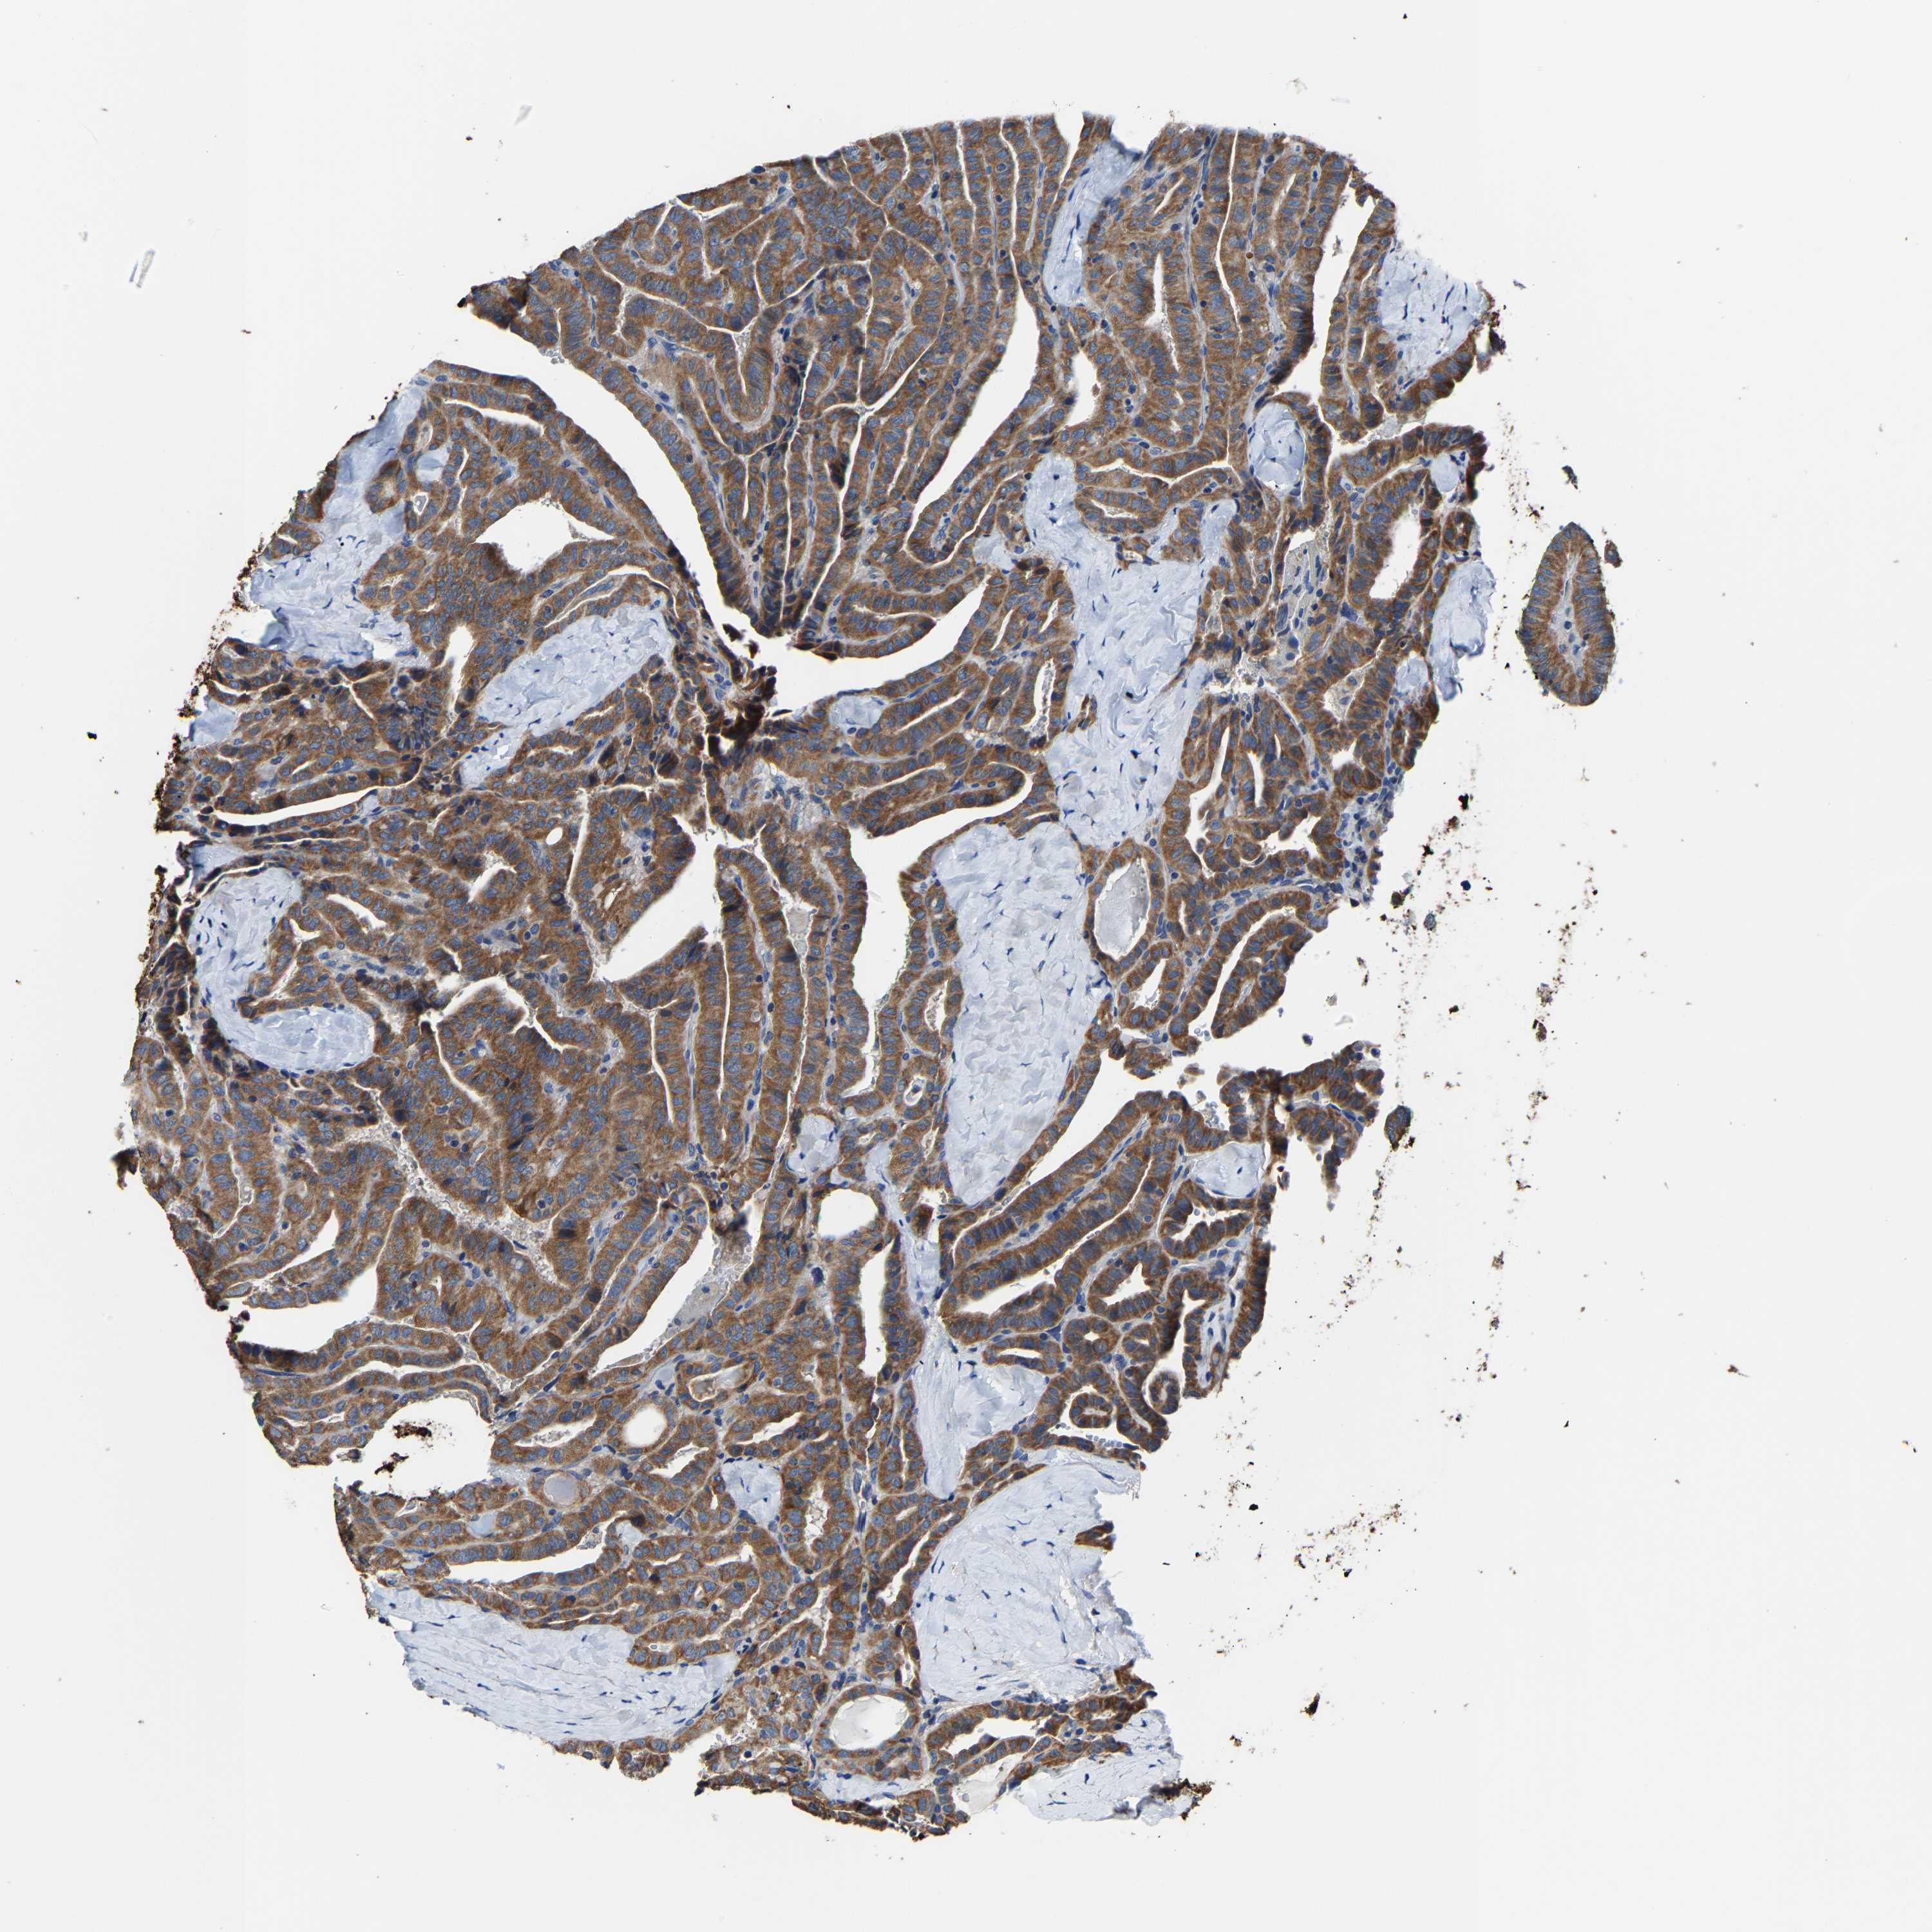

THYROID CANCER - Protein expressioni

A mouse-over function shows sample information and annotation data. Click on an image to view it in a full screen mode. Samples can be filtered based on level of antibody staining by selecting one or several of the following categories: high, medium, low and not detected. The assay and annotation is described here.

Note that samples used for immunohistochemistry by the Human Protein Atlas do not correspond to samples in the TCGA dataset.

Antibody stainingi

Antibody staining in the annotated cell types in the current human tissue is reported as not detected, low, medium, or high, based on conventional immunohistochemistry profiling in selected tissues. This score is based on the combination of the staining intensity and fraction of stained cells.

Each image is clickable and will lead to virtual microscopy that enables deeper exploration of all samples and also displays staining intensity scores, fraction scores and subcellular localization as well as patient and tissue information for each sample.

Antibody HPA020959

Antibody HPA053471

Staining

High

Medium

Low

Not detected

Intensity

Strong

Moderate

Weak

Negative

Quantity

>75%

75%-25%

<25%

None

Location

Nuclear

Cytoplasmic/membranous

Cytoplasmic/membranous,nuclear

Papillary adenocarcinoma, NOS

Follicular adenoma carcinoma, NOS